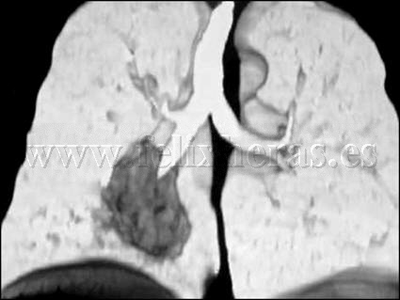

Cáncer de pulmón